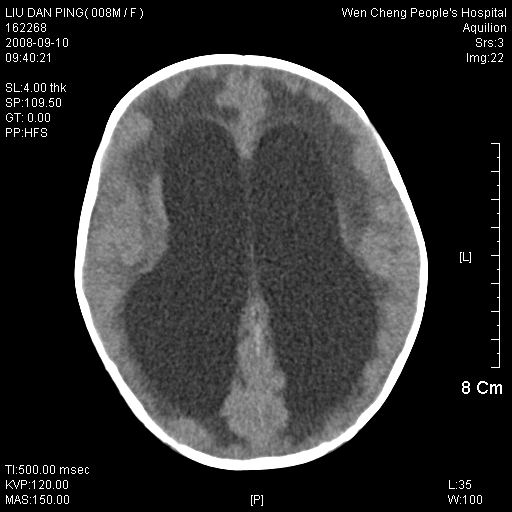

以下是引用卜一在2008-9-10 16:21:00的发言:[br]髓母细胞瘤伴梗阻性脑积水!支持![br]髓母细胞瘤特点:—般直径大于3.5cm,位于后颅凹中线之小脑蚓部。累及上蚓部的肿瘤延伸到小脑幕切迹之上,ct平扫肿瘤多呈均匀一致的高或等密度病灶,增强检查呈均匀一致的强化。病灶中有小坏死时,平扫亦可呈不均匀之混杂密度,注药后有增强。[br]

以下是引用zjzjr在2008-9-10 15:09:00的发言:[br]髓母细胞瘤伴梗阻性脑积水.